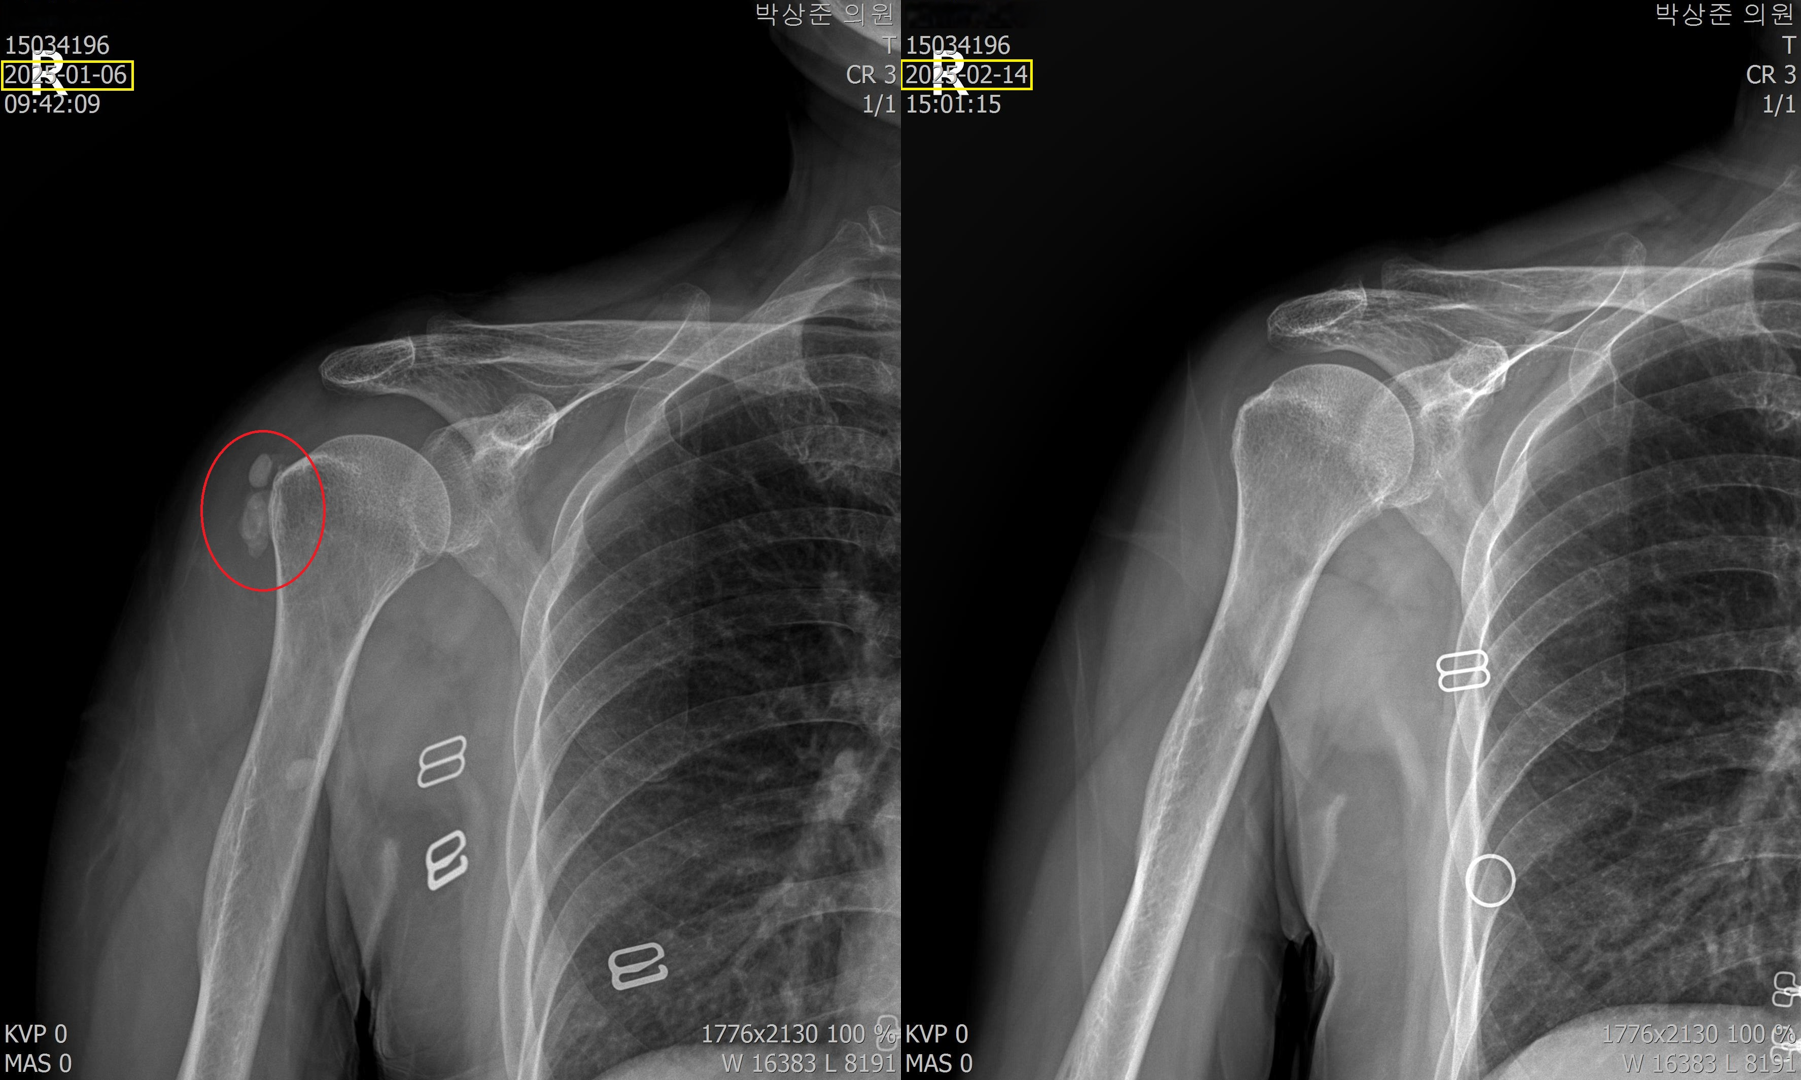

이렇게 5회 정도를 제거하고 찍은 비포 & 애프터 사진입니다. 최초의 빨간 동그라미 안의 석회가 거의 다 사라지고 약간 뿌연 정도로만 남아있는걸 확인할 수 있습니다. 이분은 이 치료 후 통증이 90% 가량 호전되었고 남은 통증은 시간이 지나면서 서서히 줄어들어서 지금은 통증이 거의 없는 상태로 지내고있습니다.